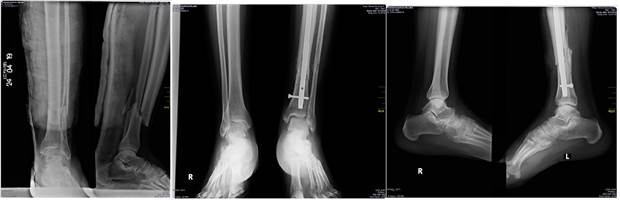

En relación a la colocación de la fijación intramedular en las fracturas del tercio distal de la tibia, es importante evitar la angulación en valgo, que puede lograrse mediante tres métodos; primero: fijación del peroné para alinear el bloque distal de la tibia antes de la colocación del clavo; segundo: emplear tracción calcánea o distractor femoral para lograr corregir la angulación antes de la colocación del dispositivo; tercero y último: es colocar el alambre guía en el centro del fragmento distal de la fractura antes de rimar, este paso puede ser apoyado mediante la transfixión de un alambre de Steinmann paralelo a la superficie articular del fragmento distal, que además ayuda a la reducción (Figura 2). 21,22

En caso de optar por la fijación externa definitiva se debe tener especial cuidado en el control rotacional y angular de la fractura mediante la realización de radiografías seriadas, esta posibilidad está bien justificada en enfermos con presencia de conminución extensa de localización metafisaria y diafisaria con o sin afección articular (Figura 3) 27,29